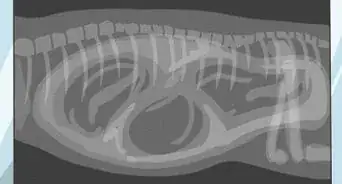

• The vet might use an endoscope, which is a fine tube with a fiberoptic camera, passing it up the nose to check that it is a foxtail that is causing the problem.

• The vet can remove the foxtail using forceps or a grasper on the endoscope. A vet's forceps will have much longer and narrower arms than tweezers at home.

• The vet might flush the nasal cavity to remove all nasal debris.